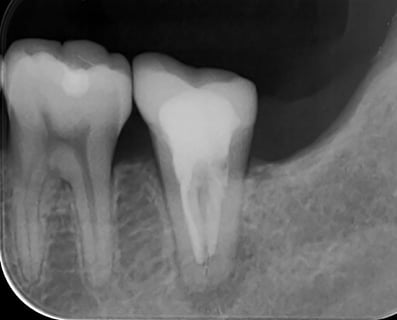

このような状態になるまで、根管の中を綺麗にしていきます。実はこの作業は非常に難しいです。図の右の凸部は歯なのですが、この裏には歯槽骨(骨)が入り込んでいて、薄皮1枚みたいな状態です。これに穴をあけると、また別の問題が生じます。

約1ケ月後ですが、根の先の炎症の証である透過像は、消失し、噛むと痛いなどという臨床症状も消えました。